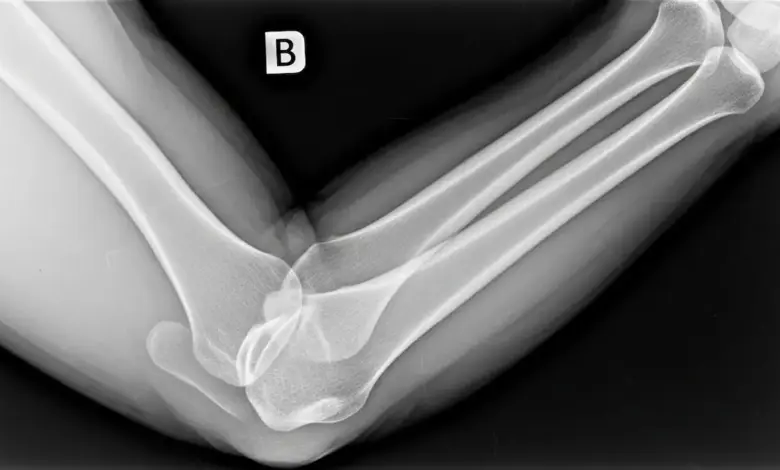

Na prática, existem sinais bem característicos que ajudam a suspeitar do problema, mas a confirmação depende de exame físico e imagem, como radiografia.

Como é feito o diagnóstico

O diagnóstico combina:

- Exame físico, avaliando deformidade, estabilidade, dor localizada e função nervosa/vascular.

- Radiografia, essencial para confirmar o quadro e pesquisar fraturas associadas.

- Tomografia em casos selecionados, principalmente quando há suspeita de fraturas pequenas ou para planejamento terapêutico.